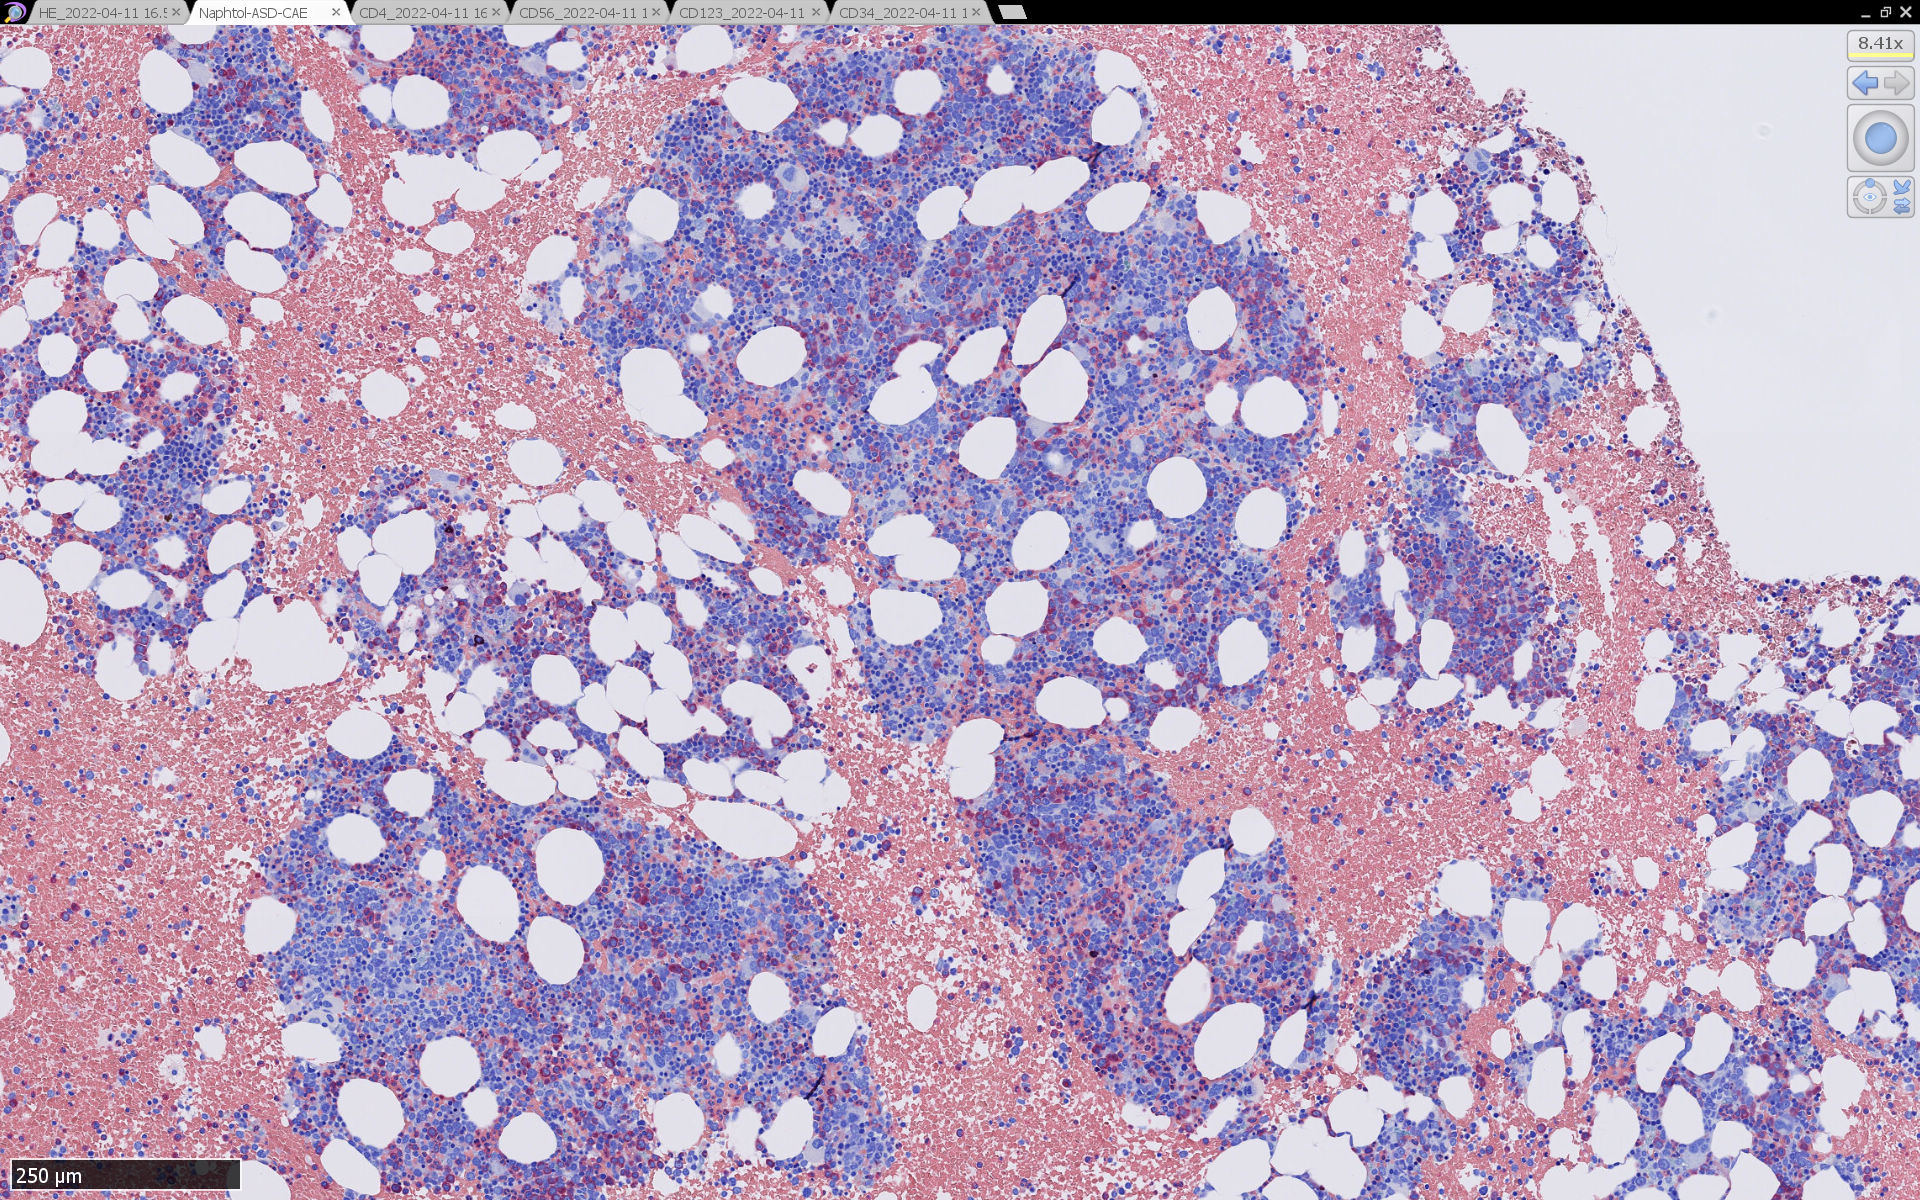

骨髄病理所見

HEでは腫瘍細胞の同定が難しい. 本症例は ASD-Giemsa染色を見ても, 腫瘍胞巣はよくわからなかった. 皮膚が先に診断がつき, 次いでBone marrowだったため, 免疫染色にすすめたが, Bone marrowが先だと診断に困ったかもしれない. 本例は, 骨髄がhypercellularで, dysplastic hematopoiesisがありMDSも疑われている.

免疫染色

CD4は染まりすぎの感がある(濃く染まる細胞はCD4+ T-cellかもしれない). CD56, CD123が陽性で可能性が高くなり, BPDCNの診断にはCD34は陰性であることが必要

TCF4、CD123、TCL1をconsultationにより染色していただき, 陽性を確認した. CD34-, lysozyme-, CD123(おいてある病院は少ないかも)をしらべて, BPDCN研究会あてconsultationをする流れでしょうか.

BPDCN骨髄病変の病理

症例骨髄に認められた異形成造血所見

Mgkは低分葉, 円形単核の細胞が多く, 分離円形核のMgkもみられた. 赤芽球はproerythroblstsのみの小集簇や孤在性出現あり. 成熟赤芽球が乏しい. 顆粒球系細胞も分葉好中球への分化像が少ない.

免疫染色では, HbFを発現する赤芽球の集簇巣が散見しているほか, p53陽性細胞が軽度に増加している. CD34陽性細胞増加はなし.CD42b染色でmicroMgkはみられなかった. 異形成造血が強く疑われる.